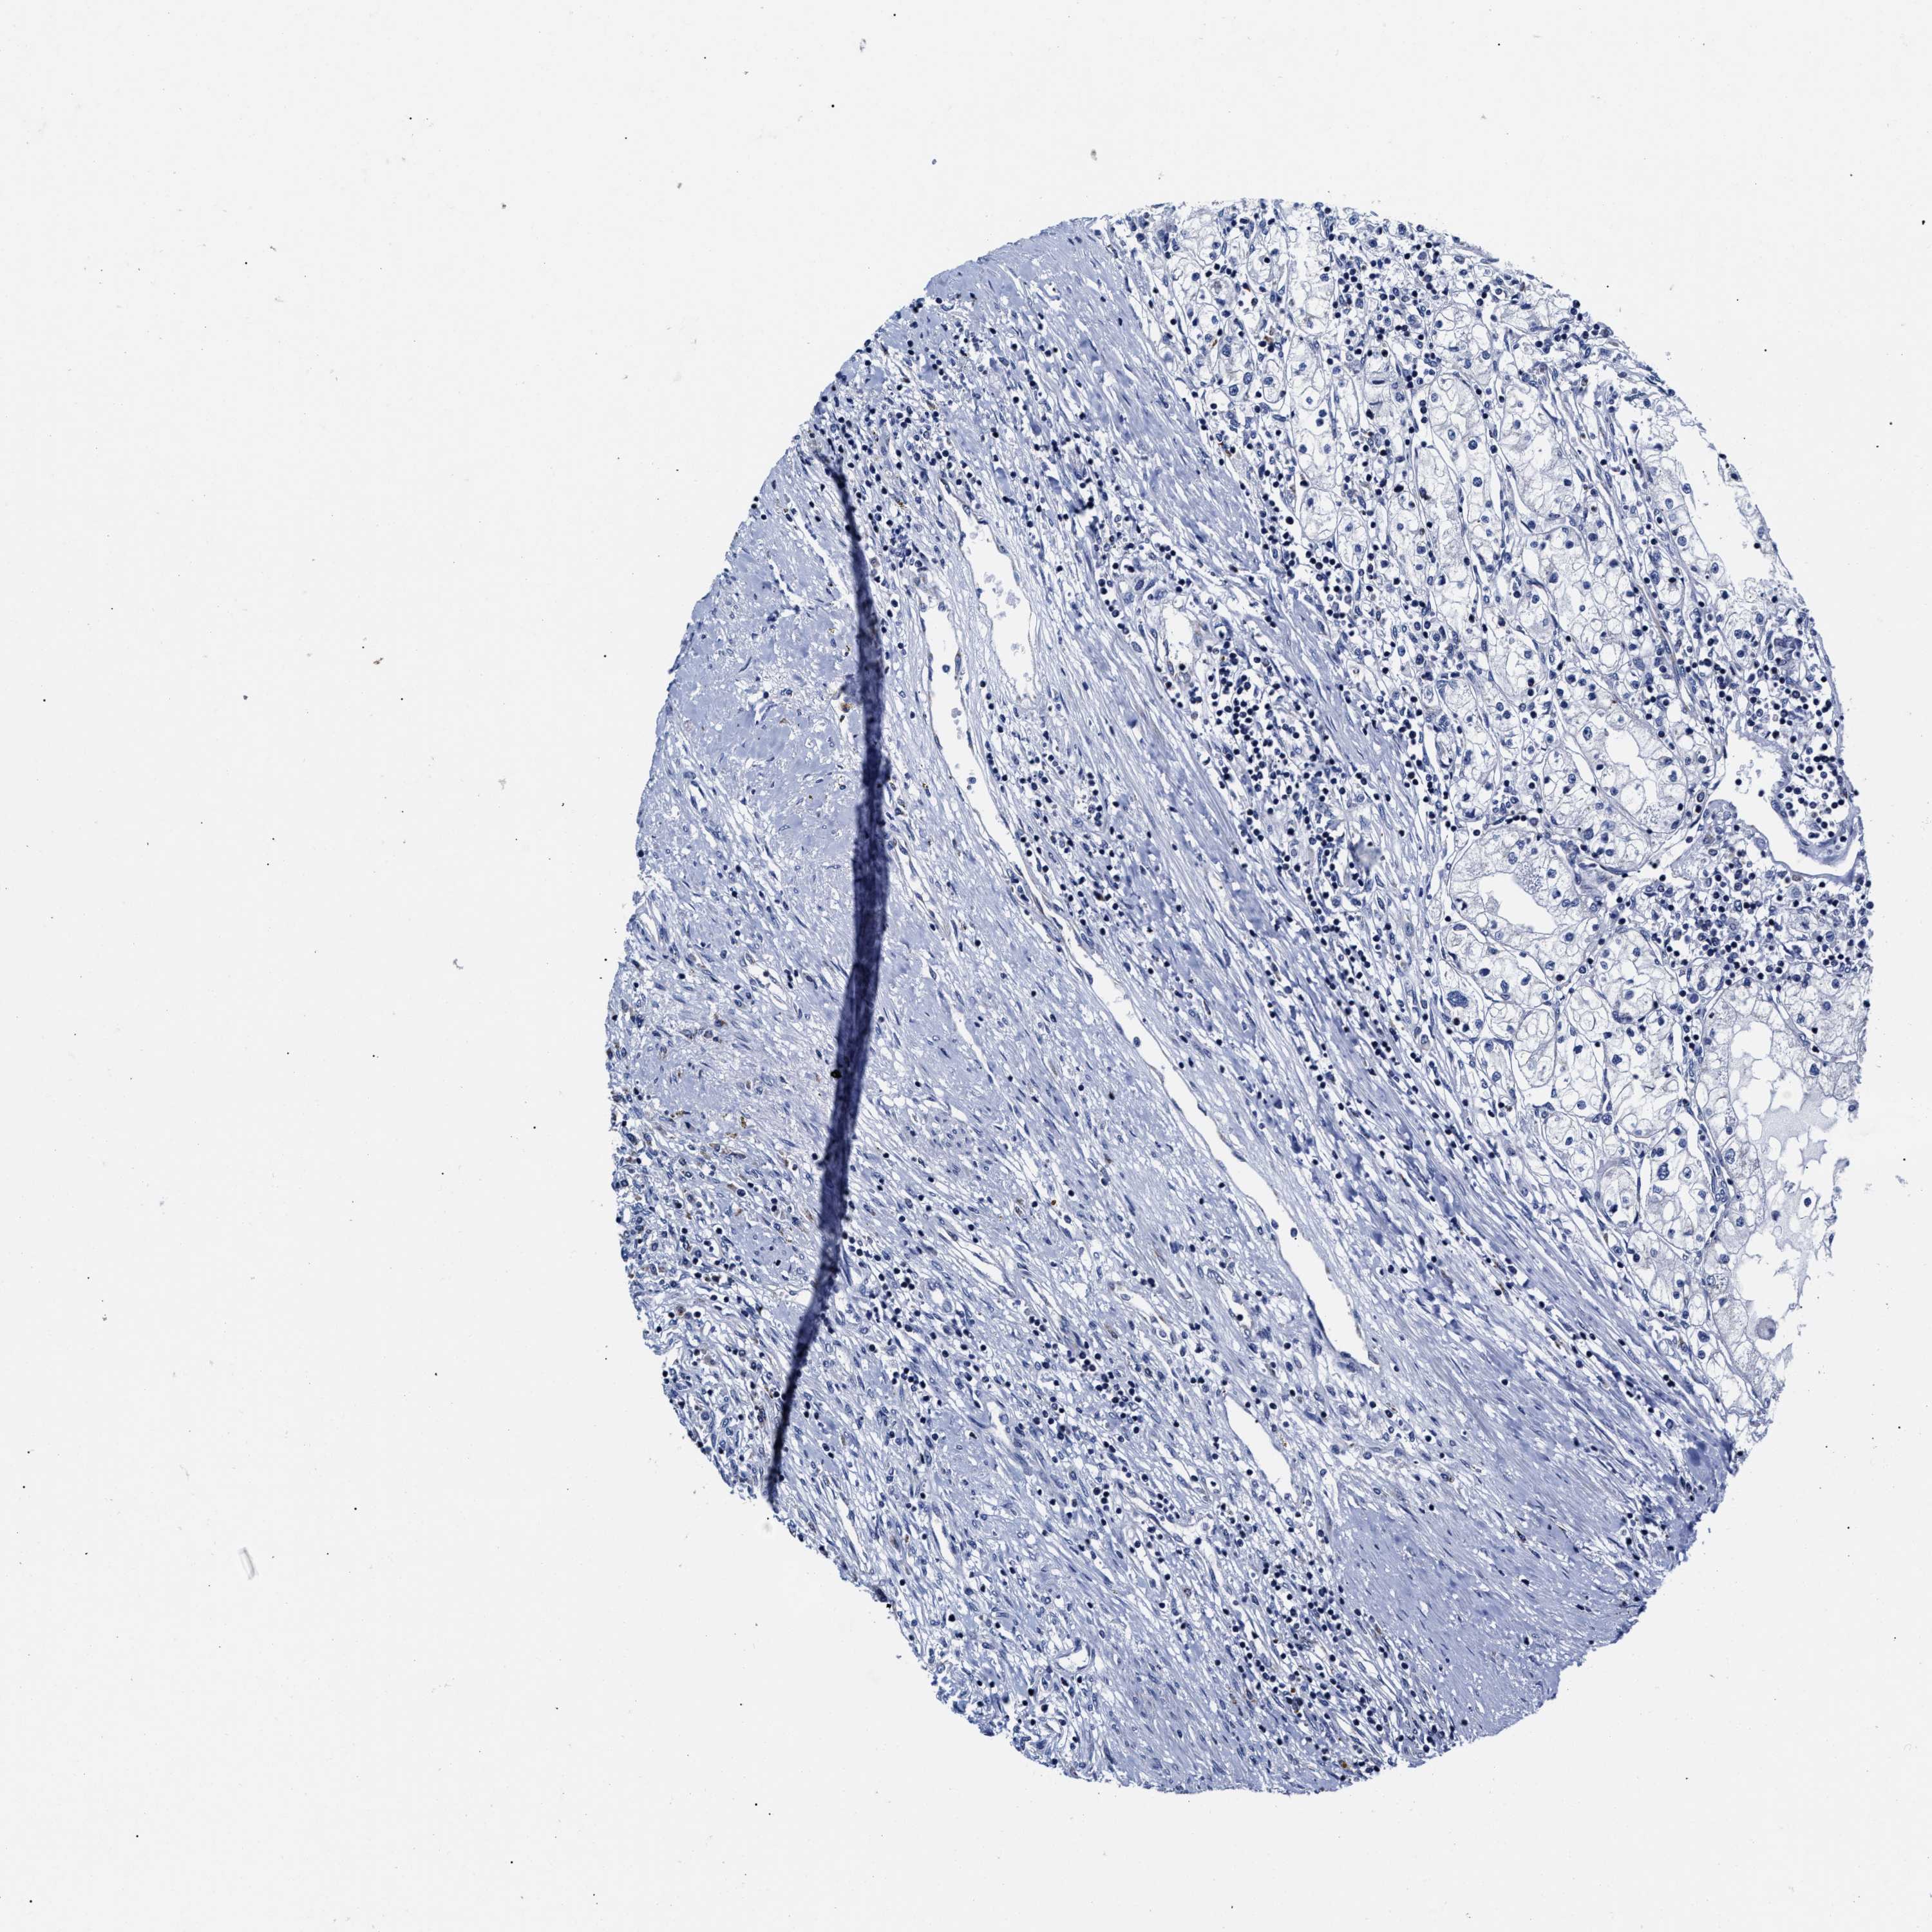

KIDNEY RENAL CLEAR CELL CARCINOMA (TCGA) - Interactive survival scatter ploti

The Survival Scatter plot shows the clinical status (i.e. dead or alive) for all individuals in the patient cohort, based on the same data that underlies the corresponding Kaplan-Meier plots. Patients that are alive at last time for follow-up are shown in blue and patients who have died during the study are shown in red.

The x-axis shows the expression levels (FPKM) of the investigated gene in the tumor tissue at the time of diagnosis. The y-axis shows the follow-up time after diagnosis (years). Both axes are complimented with kernel density curves demonstrating the data density over the axes. The top density plot shows the expression levels (FPKM) distribution among dead (red) and alive patients (blue). The right density plot shows the data density of the survived years of dead patients with high and low expression levels respectively, stratified using the cutoff indicated by the vertical dashed line through the Survival Scatter plot. This cutoff is automatically defined based on the FPKM cutoff that minimizes the p-score. The cutoff can be changed by dragging the vertical line or by entering a cutoff value in the square labeled "Current cut-off".

Under the Survival Scatter plot the p-score landscape (black curve; left axis) is shown together with dead median separation (red curve; right axis). Dead median separation is the difference in median mRNA expression between patients who have died with high and low expression, respectively. It is calculated as follows: median FPKM expression of dead patients with high expression - median FPKM expression of dead patients with low expression. This is intended to aid the user in visually exploring custom cutoffs and the associated p-scores and dead median separation.

Individual patient data is displayed and can be filtered by clicking on one or more of the category buttons on the top of the page. Categories describing expression level and patient information include: high, low, alive, dead, female, male and tumor stages. The scale of the x-axis can be toggled between linear and log-scale by clicking on the "x log" button. Mouse-over function shows TCGA ID, patient information and mRNA expression (FPKM) for each patient.

& Survival analysisi

Kaplan-Meier plots summarize results from analysis of correlation between mRNA expression level and patient survival. Patients were divided based on level of expression into one of the two groups "low" (under cut off) or "high" (over cut off). X-axis shows time for survival (years) and y-axis shows the probability of survival, where 1.0 corresponds to 100 percent.

HINT2 is potential prognostic, high expression is favorable in Kidney Renal Clear Cell Carcinoma (TCGA)

Best expression cut offi

Based on the FPKM value of each gene, patients were classified into two groups and association between prognosis (survival) and gene expression (FPKM) was examined. The best expression cut-off refers the FPKM value that yields maximal difference with regard to survival between the two groups at the lowest log-rank P-value. Best expression cut-off was selected based on survival analysis .

When clicking on this number, the vertical dashed line indicating cut-off, the interactive survival plot, and the Kaplan-Meier curve will be adjusted to show results based on the best expression cut-off.

: 36.64

TCGA RNA samplesi

RNA-seq data is reported as average FPKM (number Fragments Per Kilobase of exon per Million reads), generated by the The Cancer Genome Atlas (TCGA) .

Normal distribution across the dataset is visualized with box plots, shown as median and 25th and 75th percentiles. Points are displayed as outliers if they are above or below 1.5 times the interquartile range. FPKM values of the individual samples are presented next to the box plot.

Average pTPM 53.1

Number of samples 521